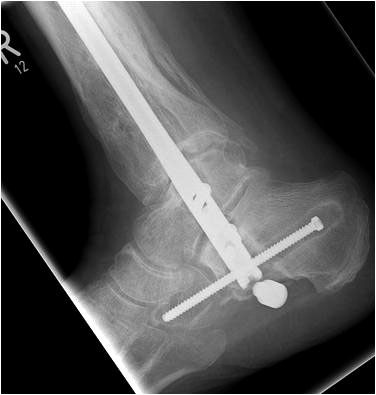

Implantation des Nagels und BV-Kontrolle (Video 5). Schließlich erfolgt die Verriegelung des Nagels über entsprechende Zielvorrichtungen. Bei einigen Nageltypen gibt es nageleigene Kompressionsmechanismen, die eine zusätzliche Drucksteigerung im Bereich der Arthrodeseflächen des ehemaligen oberen und unteren Sprunggelenkes erlauben (Video 6). Die abschließende BV-Kontrolle in beiden Ebenen sollte eine regelrechte Stellung der Arthrodese mit 90° - Stellung im Rückfuß, in der anderen Ebene mit einem Rückfußvalgus von ungefähr 5° zeigen.

Von plantar aus nun Incision und Vorschießen eines 3er KDs durch Calcaneus, Talus bis in den Tibiaschaft hinein. BV-Kontrolle in beiden Ebenen. Bei korrekter Lage nun Eröffnungsbohrung. Wechsel auf einen Draht mit Olive. BV-Kontrolle in beiden Ebenen. Über den stumpfen Draht nun Aufbohren mit flexiblen Bohrern. Der letzte Bohrerdurchmesser sollte den Durchmesser des Arthrodesenagels um mindestens einen Millimeter übersteigen.

• Pseudarthrose (Abbildung 15).

• Auswandern einzelner Schrauben (Abbildung 16).

• Verlust der Verschlusskappe (Abbildung 16).